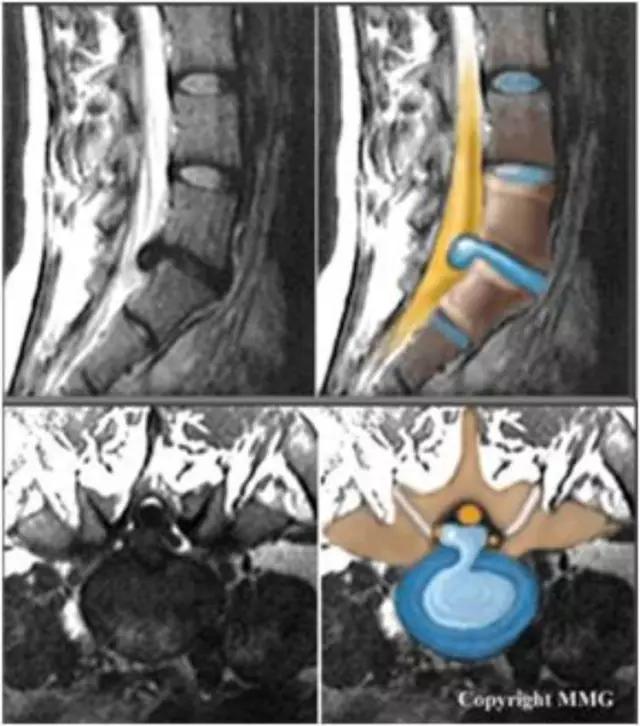

2、脊髓

半月板损伤的分度——

Normal:正常的半月板为均匀的低信号。Grade1:半月板内部小灶性的类圆形信号增高影,未达半月 板表面,代表退变性改变。Grade2:半月板内部线形的中等信号增高影,未达半月板表面,代表退变性改变。Grade3:达到半月板关节面的异常信号,可为线形或不规则形,通常代表半月板撕裂。韧带损伤的分级(对所有韧带适用)——Grade1:韧带内损伤,无长度改变。Grade2:韧带内损伤并长度延长。Grade3:完全性韧带撕裂。